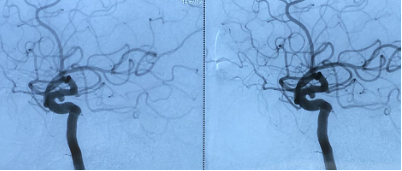

治疗过程:患者多参数监护仪监测下,全麻满意后,常规消毒铺巾,采用改良Seldinger技术穿刺右侧股动脉成功,置入8F动脉鞘。经右侧股动脉鞘,黑泥鳅带领长鞘(Penumbra Neuro MAX6F )到达右侧颈内动脉岩段,撤下泥鳅导丝,微导丝(Synchro 0.014 in*200 cm)带领支架微导管(Prowler Select Plus)达右大脑中动脉M1段,撤出微导丝,再次用微导丝(Synchro 0.014 in*200 cm)带领微导管(Echelon10eV3)超选到达眼动脉段动脉瘤内,退出微导丝。经Echelon10微导管送入(Codman COMPLEX XTRASOFT 3 mm×8 cm)弹簧圈一枚成篮并未解脱,后经支架微导管释放支架一枚(Codman ENTERPRISE 4.5 mm*22 mm)支架打开良好,覆盖瘤颈,撤出支架微导管后解脱首枚弹簧圈,复查造影,弹簧圈位置形态良好,解脱后继续送入(Codman COMPLEXXTRASOFT 2.5 mm×3.5 cm; EV3 3D 1 mm×2 cm;EV3 3D 1.5 mm×4 cm)3枚弹簧圈,期间间断造影确保眼动脉段血流通畅,栓塞后复查脑血管造影,动脉瘤区未见显影,未见造影剂渗漏。手术结束。缝合器缝合右股动脉穿刺点,加压包扎。术后患者麻醉清醒,拔除气管插管,呼唤应答,对答切题,言语清楚,四肢肌力肌张力正常。

术中栓塞: